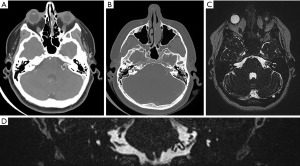

On examination, she was neurologically intact with a Glasgow Coma Scale (GCS) of 15. Unterberger’s test was negative. Preoperative pure tone audiometry showed normal hearing and speech discrimination in both ears with type A tympanograms consistent with normal middle ear function. Computed tomography (CT) of the brain demonstrated no significant widening of the left internal acoustic meatus compared to the contralateral side (Figure 1). CT angiography and magnetic resonance imaging (MRI) also revealed a complex 20 mm × 9 mm × 7 mm nidus of blood vessels in the left intracanalicular portion of the internal acoustic meatus extending into the cerebellopontine angle (Figure 1). There was a meatal loop arising from the anterior inferior cerebellar artery (AICA).

Cerebral digital subtraction angiography (DSA) confirmed the presence of a left internal acoustic meatus AVM with primary feeders from the left AICA and left posterior inferior cerebellar artery (PICA). Venous outflow was via cerebellar veins draining to the left sigmoid sinus (Figure 2). Given the majority of the arterial supply appeared to be from the endovascularly accessible single trunk AICA, this artery was cannulated and the feeding branch was preoperatively coiled. The left PICA was also cannulated but multiple small perforators were seen to be supplying the AVM and these were deemed too high risk to occlude. Post-embolization angiography on the 29th August 2022 demonstrated significantly reduced flow through AVM but some residual supply arising from branches of the teloveloteonsillar segment of the left PICA (Figure 2). Immediately following the endovascular embolization the patient developed a new complete left sided sensorineural hearing loss likely due to involvement of the labyrinthine artery during the procedure.

Post-operative cerebral angiography demonstrated successful complete obliteration of the AVM (Figure 3). Diffusion-weight imaging sequence revealed a small acute infarct of the left middle cerebellar peduncle likely related to endovascular embolization (Figure 4). On 3-month follow-up, she had persistent left sided sensorineural hearing loss but an improving House-Brackmann 3 palsy. She was reviewed by speech pathology both as an inpatient and outpatient given her hearing loss.